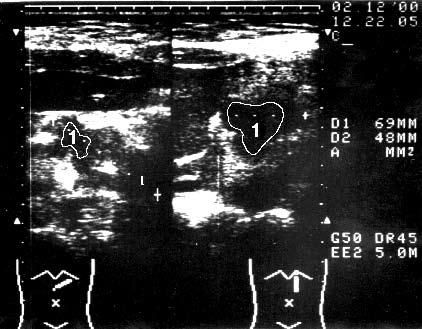

Рис. 98. Ультразвуковое исследование. Рак головки ПЖ. На снимке видна гипоэхогенная бугристая раковая опухоль 5x4 см (1)